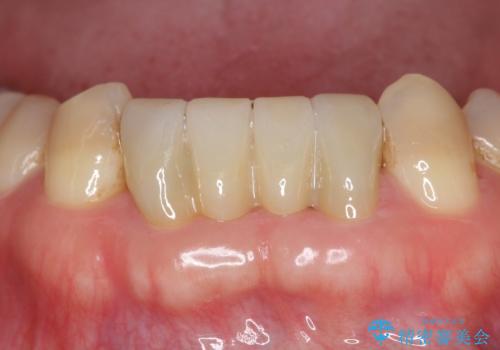

今回は、丈夫な欠けにくいフルジルコニア(ヴェレッツァ)クラウンでブリッジにすることにしました。

- 32万円(下顎2−2:フルジルコニアクラウン(ヴェレッツァクラウン・スタンダード)7万円x4本、仮歯1万円x4本)費用は治療当時の料金となります

装着後、特に問題なく使用されています。